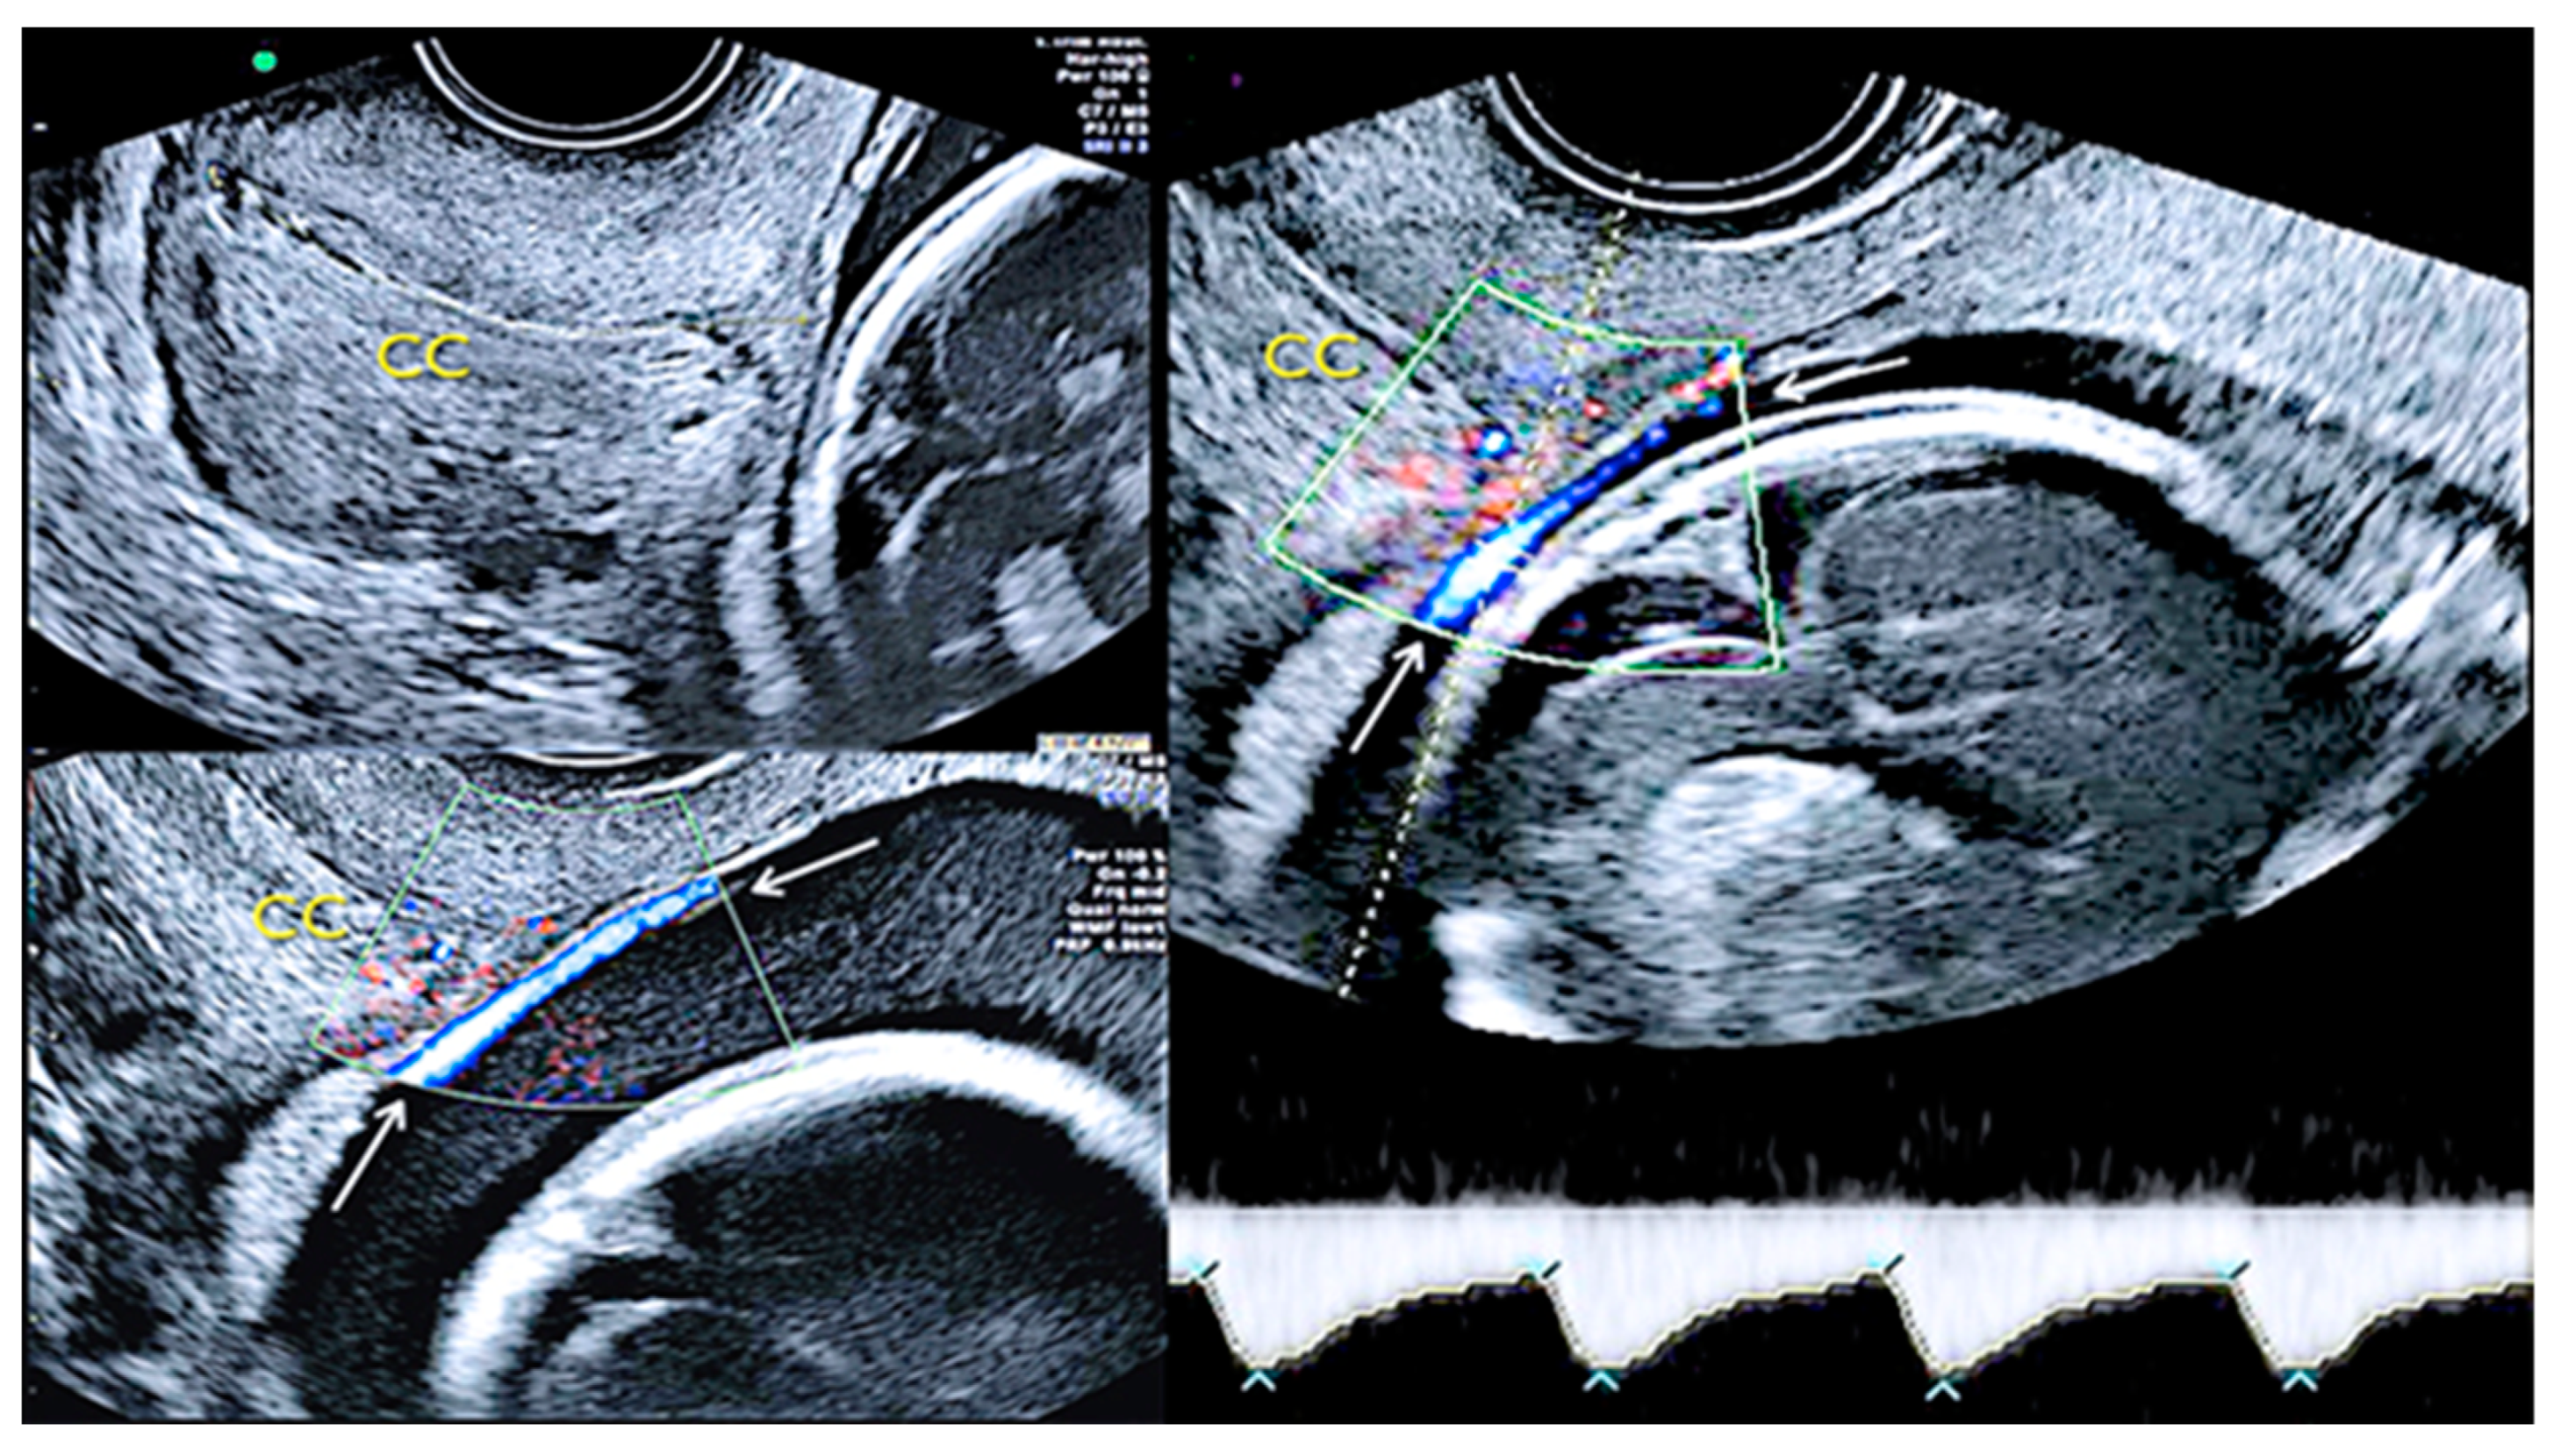

Pregnancy at 24 weeks’ gestation. Two-dimensional ultrasound, color and pulse wave (PW) spectral Doppler ultrasound allowed the detection of an arterial vessel close to the internal cervical os (vasa praevia Type III, white arrows)(Legend: CC: cervical canal).

3.2.3. Velamentous Umbilical Cord Insertion